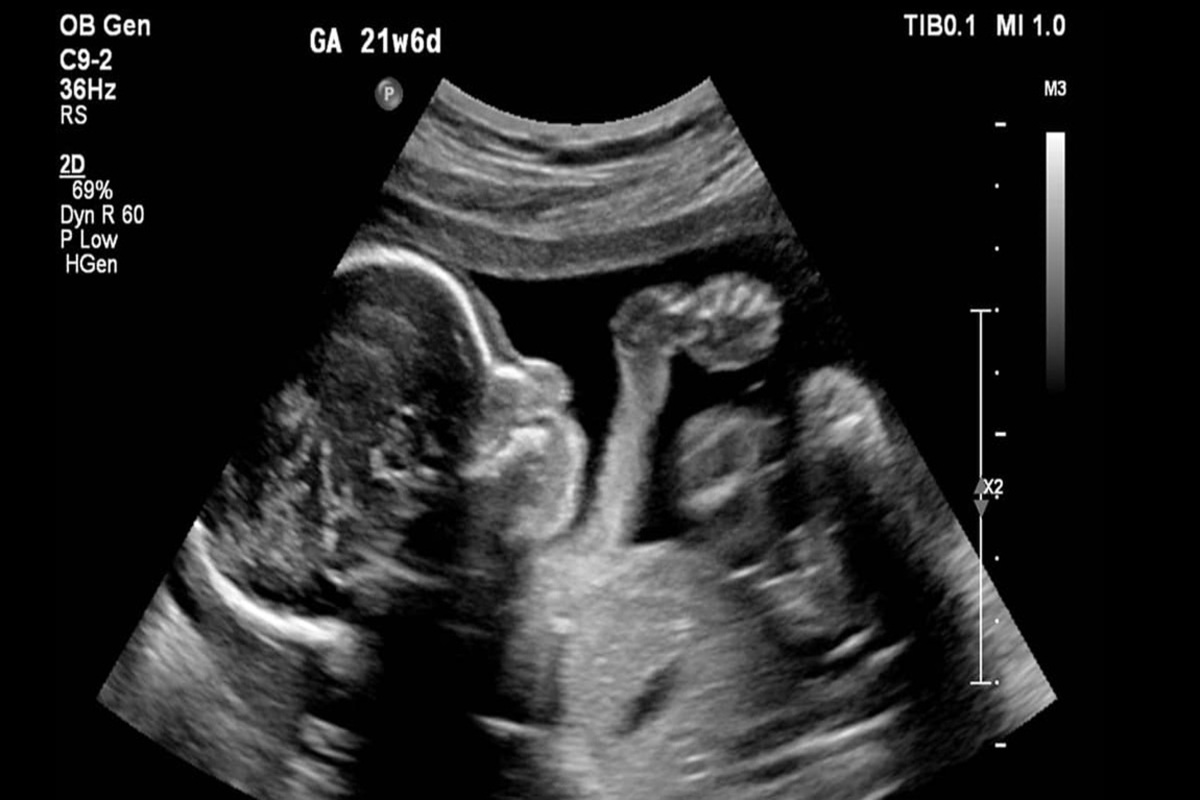

کیهان: زنان با چه استدلال هایی حاضر به سقط جنین می شوند؟

کیهان نوشت: بر اساس پژوهشی که پژوهشکدة علوم بهداشتی جهاد دانشگاهی انجام داده، به دست آمده که مشکل مالی و اقتصادی، اختلاف با شوهر، جنسیت جنین، فاصلة کم بین بارداری‌ها، سن کم مادر، سن بالای مادر، تعداد زیاد فرزندان، گرفتاری شغلی مادر، اعتیاد شوهر، بارداری در ابتدای ازدواج یا در دوران عقد و... از عواملی هستند که در بارداری ناخواسته، سبب می‌شوند که مادر تصمیم به سقط جنینش بگیرد.

این دلایل موجب می‌شوند که برخی مادران، به خود حق بدهند و خود را قانع کنند که جنینشان را سقط کنند و معمولاً هم تنها چیزی که ذهنشان خطور نمی‌کند یا جدی نمی‌گیرند، نگاه شرع مقدس اسلام به این عمل است؛ در حالی که از دیدگاه فقه شیعه، سقط جنین از روی عمد، حرام است و در این حکم، اختلافی میان آنها نیست و فرقی هم نیست بین این که جنین از راه مشروع ایجاد شده باشد یا نامشروع؛ همچنین بنا به اجماع فقها در حرمت سقط جنین، فرقی میان مراحل مختلف جنین نیست؛ بنابراین، پس از انعقاد نطفه و استقرار نطفه در جدار رحم که مبدأ رشد جنین است، سقط آن حرام می‌شود.

سقط جنین، خواه قبل از دمیدن روح در جنین باشد یا بعد از آن و خواه با رضایت والدین باشد یا بدون رضایت آنها، در همة این حالات حرام است. البته ناگفته نماند بعضی فقهای شیعه سقط جنین را در مواردی مجاز دانسته‌اند مثل موردی که سلامتی مادر در خطر باشد یا جنین ناقص باشد و...؛ اما همین موارد مجاز هم بی‌در و پیکر و بی‌قاعده و ضابطه نیست؛ شروط متعددی باید در کار باشد تا چنین کاری مجاز شمرده شود.